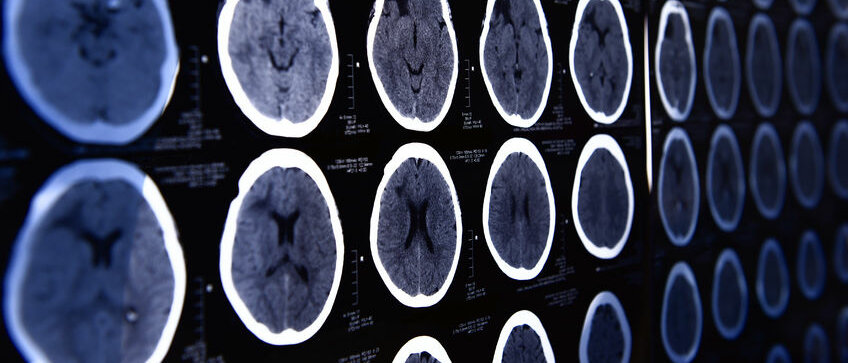

Neue Wege in der Therapie – Versorgungsaspekte und Qualitätssicherung bei der Thrombektomie

Im Gegensatz zur Nachsorge ist Deutschland in der Akutversorgung von Schlaganfallpatienten schon jetzt sehr gut aufgestellt: So wird die mechanische Thrombektomie (MTE) fast flächendeckend gewährleistet. „Die Thrombektomie kann schwere Behinderungen nach einem Schlaganfall verhindern, da verstopfte Hirnarterien mittels eines Mikrokatheters von einem großen Blutgerinnsel befreit werden“, erläutert Professor Dr. med. Darius Nabavi, Vorsitzender der Stroke Unit Kommission der DSG und Chefarzt der Klinik für Neurologie am Vivantes Klinikum Neukölln in Berlin. „Die Thrombektomie gilt seit drei Jahren als fest etablierte Therapie“, so Professor Dr. med. Martin Dichgans, 1. Vorsitzender der DSG und Direktor des Instituts für Schlaganfall- und Demenzforschung (ISD) am Klinikum der Universität München.